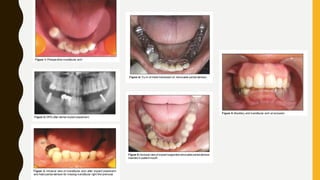

IMPLANT ASSISTED RPDS

• improve support, retention, and stability of the prosthesis while

maintaining alveolar height in the region where the implant is

placed.

• improve the oral health quality of life for patients.

• benefit of is significant in distal extension scenarios (Kennedy class

I and II), as it efficiently serves to improve support, creating a tooth-

supported situation (Kennedy class III).

• minimizes the potentially damaging class I lever force that is placed

on the distal abutment tooth during function.

• economical and beneficial rehabilitation that significantly improves patient satisfaction.

Anteriorly

placed implant

may improve

esthetics by

eliminating a

visible retainer

clasp.